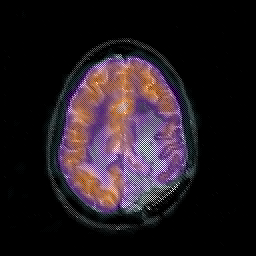

Glioblastoma multiforme overlay -- Slice #38

[Home][Help][Clinical][Tour 1][Tour 2][Tour 3] Slice 38